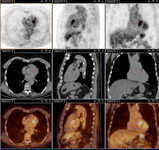

Q fever endocarditis diagnosed at PET scan: 18F-fluorodeoxyglucose PET/CT. In this asymptomatic patient with heart valve history with elevated serology, the PET scan diagnosed an aortic endocarditis on native valve with thoracic and lumbar aortic mycotic aneurysms

Institut Hospitalo-Universitaire Méditerranée Infection (patient consent obtained)

Q fever aortic mycotic thoracic aneurysm diagnosed at PET scan: 18F-fluorodeoxyglucose PET/CT. In this asymptomatic patient with heart valve history with elevated serology, the PET scan diagnosed an aortic endocarditis on native valve with thoracic and lumbar aortic mycotic aneurysms